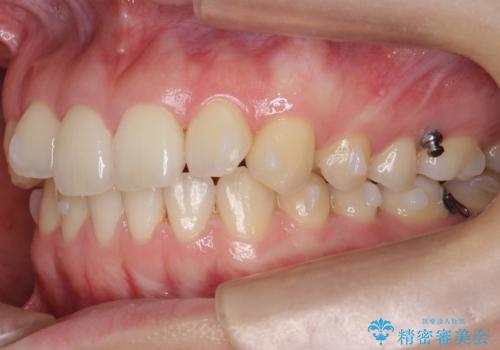

下の前歯が1本短い インビザラインと部分矯正の組み合わせ

- 前歯のガタつきと、下の前歯が一本短いことを主訴に来院。

インビザラインのマウスピースではめる装置で歯を引っ張り出すことは難しいと説明し、下の前歯だけワイヤー部分矯正を行ってからインビザライン矯正で仕上げをしました。